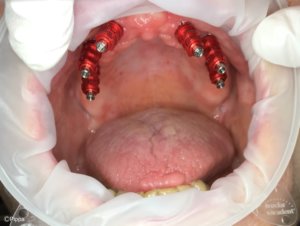

Mini-Implantate:

Die Versorgung eines zahnlosen Kiefers mit Mini-Implantaten ist ein schonendes, schmerzfreies und preiswertes Behandlungskonzept. Wie normale Implantate dienen Mini-Implantate zur Stabilisierung einer Zahnprothese und bilden die Basis für festen Zahnersatz. Mini-Implantate sind dünner als klassische Implantate und können deshalb mit geringem Aufwand eingesetzt werden. Da das Zahnfleisch und das Zahnbett bei dem Eingriff weniger beansprucht werden, verkürzt sich für Sie die Behandlungsdauer und Sie dürfen mit einer geringeren Schmerzbelastung nach der Operation rechnen.